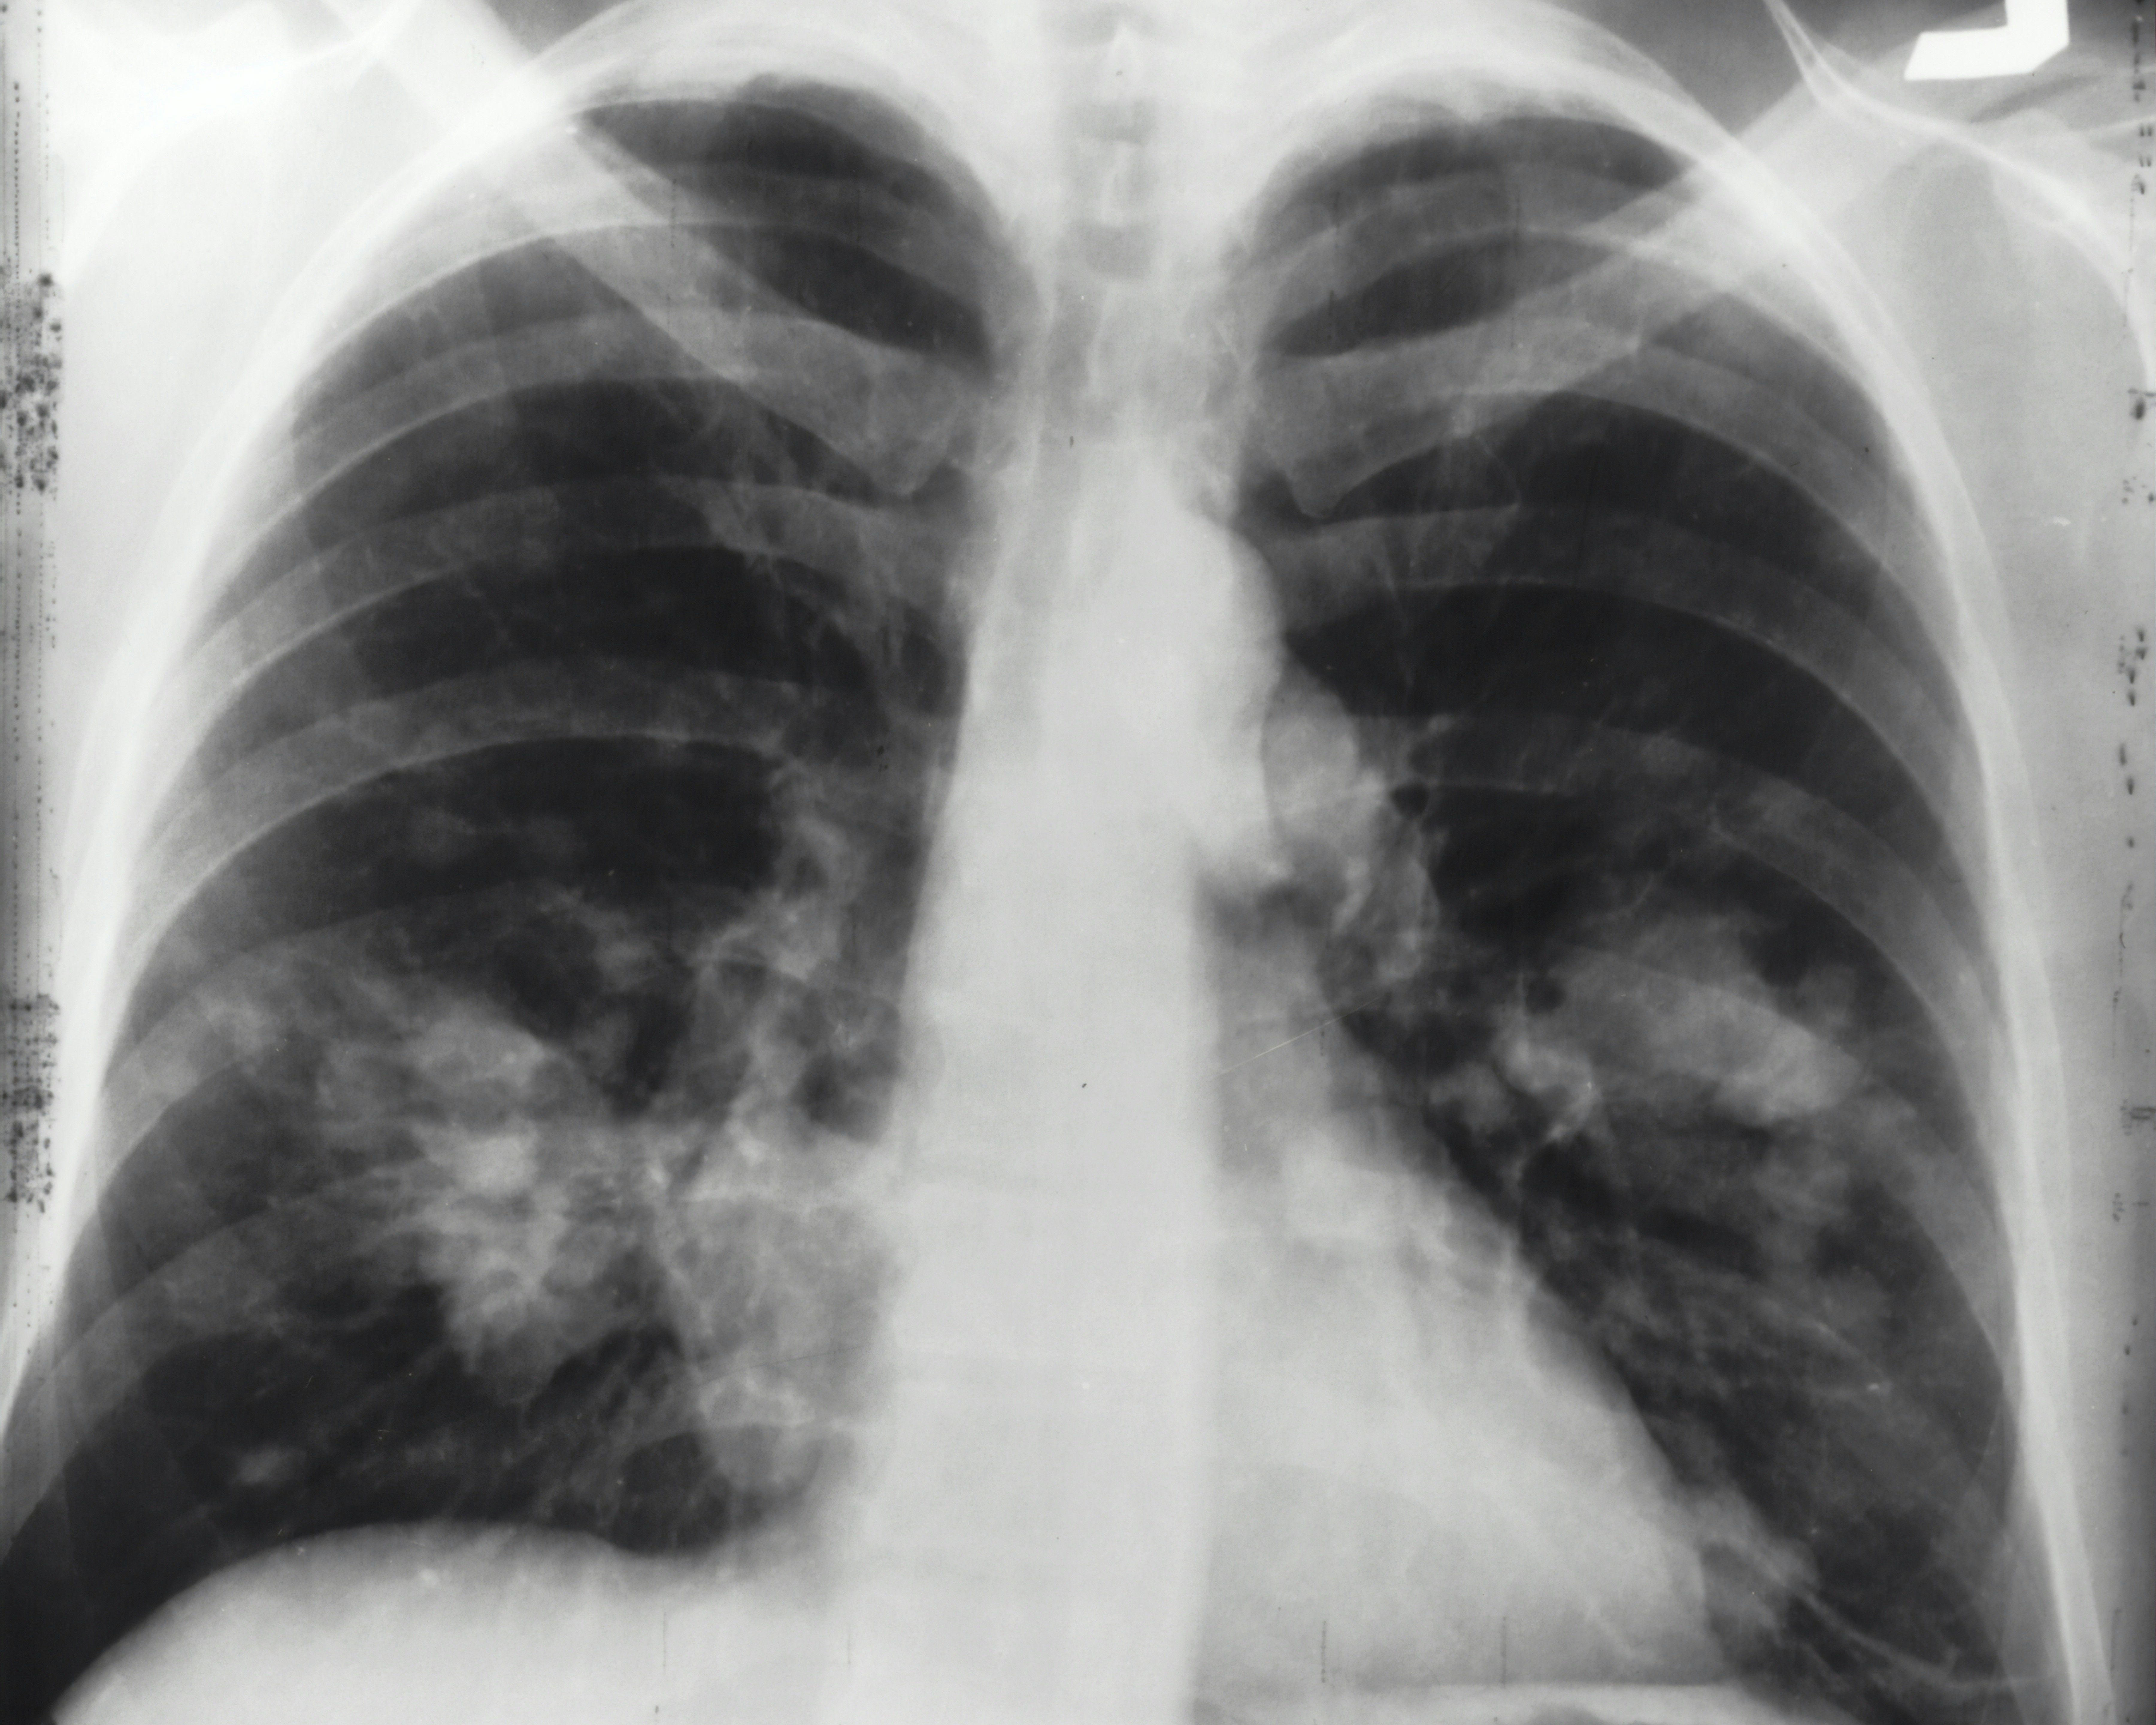

national-cancer-institute-59pGROkKJPE-unsplash An x-ray image of a chest. Both sides of the lungs are visible with a growth on the left side of the lung, which could possibly be lung cancer. Photo: National Cancer Institute / Unsplash